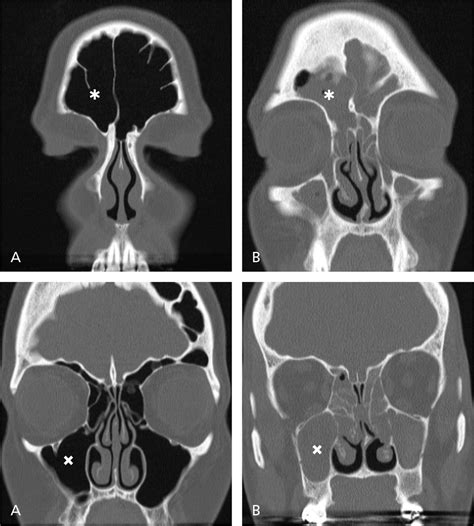

Once the images are captured, a radiologist will review them and generate a report. They look for specific markers of health, such as clear, air-filled sinus cavities, versus signs of pathology, such as fluid accumulation, mucosal thickening, or bone erosion. Your ENT specialist will then combine these results with your clinical symptoms to make a definitive diagnosis.